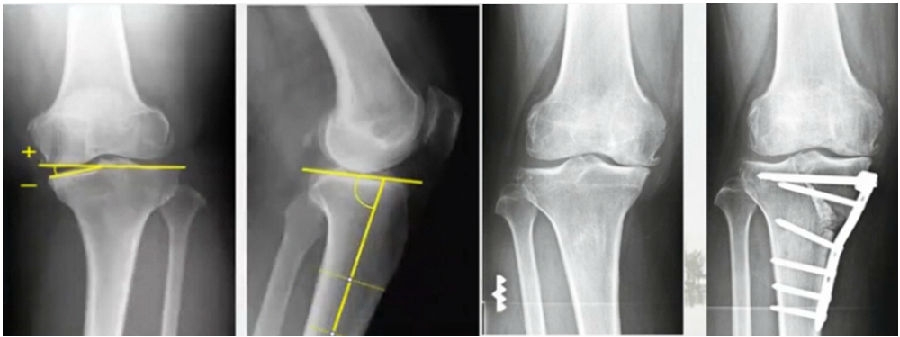

典型病例,男性,65岁,农民,双膝内翻16度。

术前影像

第一次为该患者做了传统上行开放截骨,撑开角度较大,术后用三种方法测量髌骨高度,发现髌骨高度受到影响,髌骨变低了。

左膝上行OWHTO(初次)

上行OWHTO髌骨高度测量

ISI法测量髌骨无明显变化;CDI、BPI法测量髌骨降低明显;患者屈膝锻炼困难。

第二次来院做另一侧肢体时,采用下行截骨,术后患者髌骨高度,无论用哪种方法测量都无明显变化,而且患者膝关节功能迅速得到恢复。

右膝下行OWHTO(再次)

下行OWHTO髌骨高度测量

ISI法测量髌骨无明显变化;CDI、BPI法测量髌骨无明显变化;患者屈膝明显改善。